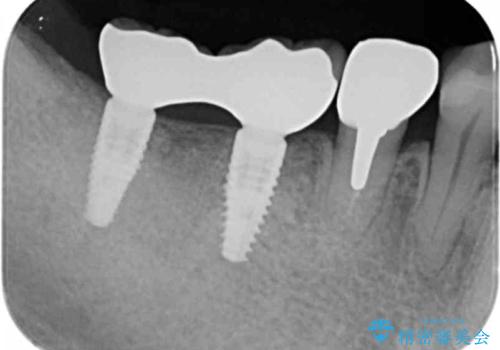

ブリッジを支える歯が割れてしまい、抜歯が必要であることと、骨の大きな吸収が見られました。

インプラント治療を行うにあたり周囲に骨を造成することで安定して噛める環境の整備を計画します。

今回はインプラント埋入時に固定が得られたので同時に骨の造成を行い治療を進めることができました。